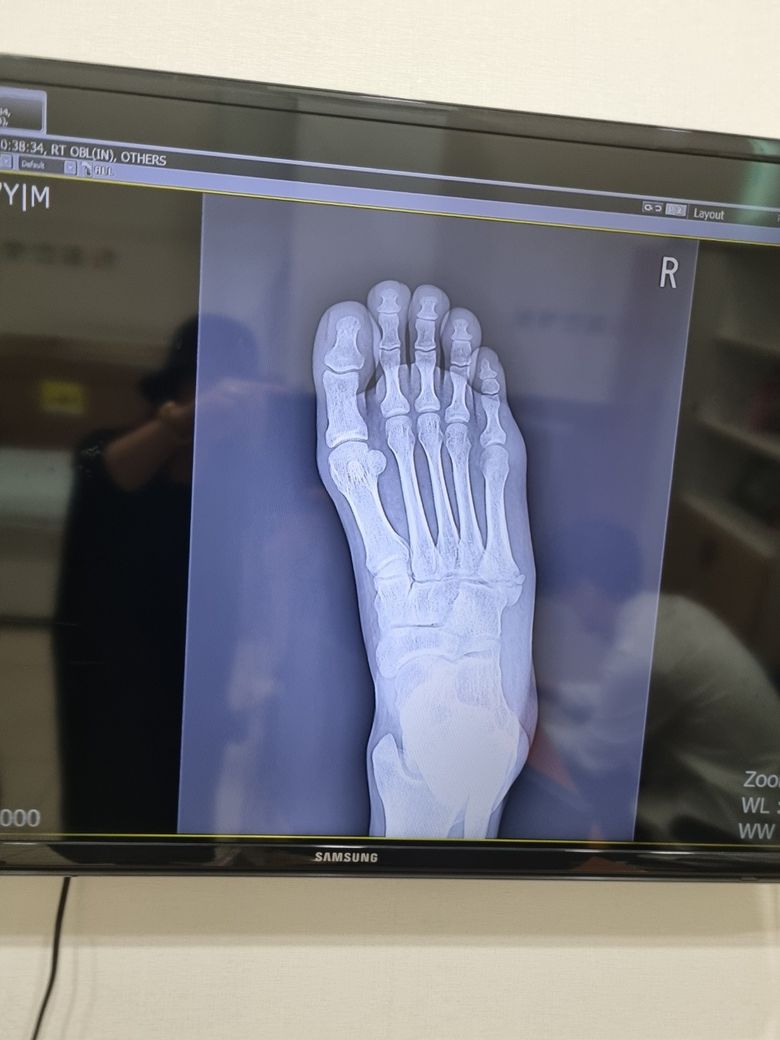

중족골의 골절인데 수술해야할까요??

2일전 발을 헛디뎌 다쳤습니다 엑스레이찍어보니 골절이라네요 수술해야된다고 하는데 꼭해야하나요??

우선 현재로썬 골절의 범위, 뼈의 어긋남 정도 등 여러 판독 결과를 통해 수술이 필요하다는 전문의에 소견을 받은것 같습니다.

2일전 발을 헛 디디면서 중족골의 골절 부상을 입으신 경우 수술 여부는 골절 부위가 크게 어긋나거나 골절이 불안정하거나 체중 부하가 어려운 경우에 수술이 필요할 수 있으며 자세한 상태는 병원에 방문하시어 상태 검사 받아보시고 상담 가져보시는게 좋을 것으로 생각됩니다.

중족골은 보행에서 체중을 지탱하는 역할을 하기 때문에 중요도가 큰데요, 때문에 골절이 발생한 경우에는 수술적 치료를 적용하는 경우가 있지만 단순히 금만 간 것이라면 보존적인 치료를 적용하기도 하니 다양한 의견을 들어보시기 바랍니다.

중족골 골절은 골절 부위, 변위 정도, 뼈의 위치에 따라 수술 여부가 달라집니다 뼈가 많이 어긋났거나 관절면에 영향을 주면 수술이 필요할 수 있고 단순 골절일면 엑스레이상 변위 정도와 걸을 때의 통증, 체중 부하 여부를 기준으로 수술 여부를 결정합니다 가능하다면 정형외과 전문의에게 2차 소겨을 받아보시는 것이 좋습니다!

대부분 수술을 하는 경우는 골절부위가 어긋났거나 중족골 관절면에 문제가 나타나는 경우 복합골절이 나타난 경우 수술을 합니다. 수술을 하지 않는 경우는 뼈가 크게 어긋나지 않거나 골절선이 단순한 경우, 체중 부하 없이 안정을 취할 수 있는 위치에 골절이 생긴 경우에는 수술을 하지 않는것이 낫습니다.

우선 CT를 촬영하셔서 좀 더 정확하게 진단을 받는것이 좋을것같습니다. CT를 찍고 수술을 안하는 경우도 많기 때문입니다.